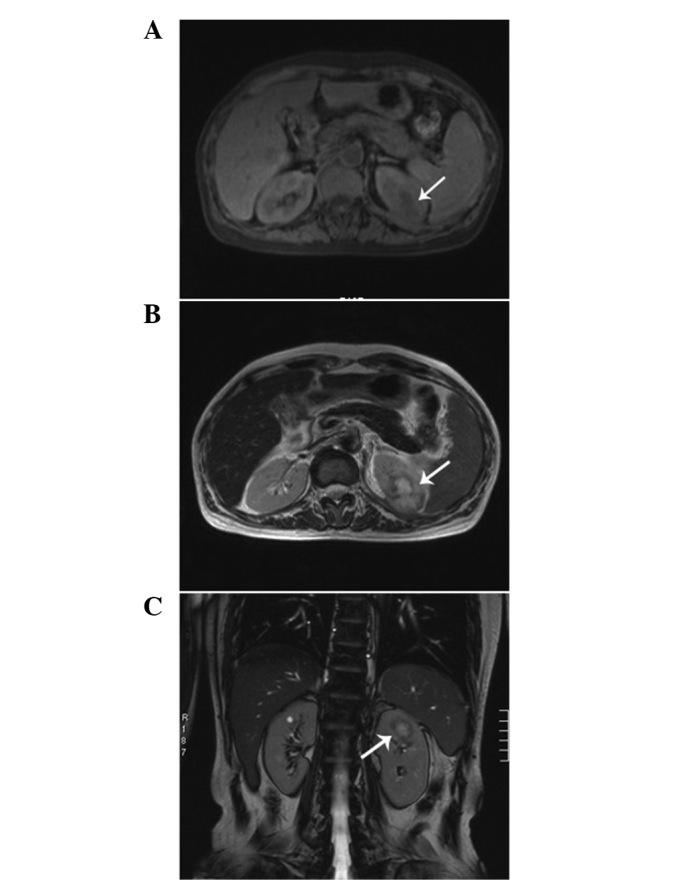

Inflammatory myofibroblastic tumor (IMT) is a rare entity that most commonly involves the lung. However, an IMT of the kidney is extremely rare. The etiology and pathogenesis of IMT remain unknown. The present study describes the case of a 48-year-old female who presented asymptomatically. Imaging investigations revealed a mass in the left kidney and a pathological examination of the nephrectomy specimen revealed an IMT. The patient had a history of trauma in the left hypochondrium 13 years previously and a history of hepatitis B for 20 years. The latter developed into hepatic cirrhosis, hypersplenism and coagulation disorders, which may play have played a significant role in the development of the IMT of the kidney in the present case and also may aid in improving the understanding of the etiology and pathogenesis of IMT of the kidney.